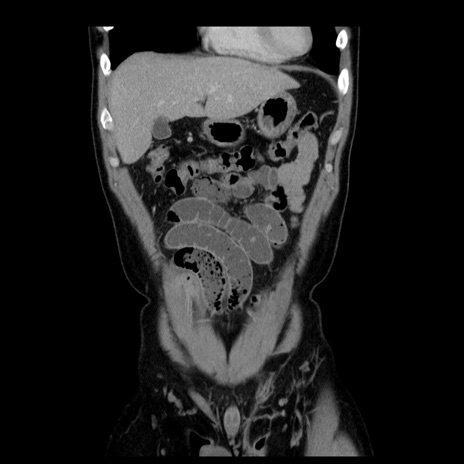

横断像

【症例】30歳代男性

【主訴】腹痛、嘔吐

【現病歴】昨晩から突然の腹痛あり、その後嘔吐、軟便も出現。腹痛が改善しないため救急搬送となる。2日前にしめ鯖の食事歴あり。

【身体所見】意識清明、苦悶様、BP 135/90mmHg、BT 35.7℃、腹部:平坦、やや硬、心窩部〜臍部に自発痛、圧痛あり、筋性防御+、反跳痛-

【データ】WBC 8100、CRP 0.57